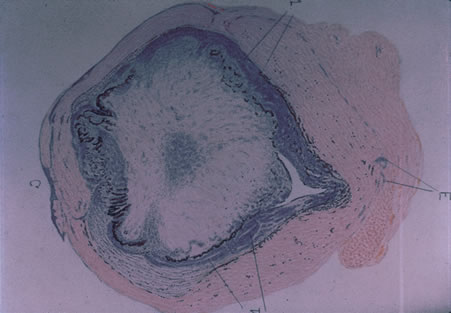

Classic histopathology consists of caseating granulomatous inflammation in a zonal distribution. The noncaseating tubercle may be present but is less specific (Fig. 18). The organism is acid-fast, meaning that it does not decolorize with acid alcohol after staining with basic fuchsin, appearing as bright red, long thin rods. A definitive laboratory diagnosis of intraocular tuberculosis may be made via anterior chamber tap, vitreous or chorioretinal biopsy depending on the site of inflammation. The PCR may be helpful in making the diagnosis.

Fig. 18. Histopathologic examination of an enucleated eye demonstrates a caseating focus in the choroid.